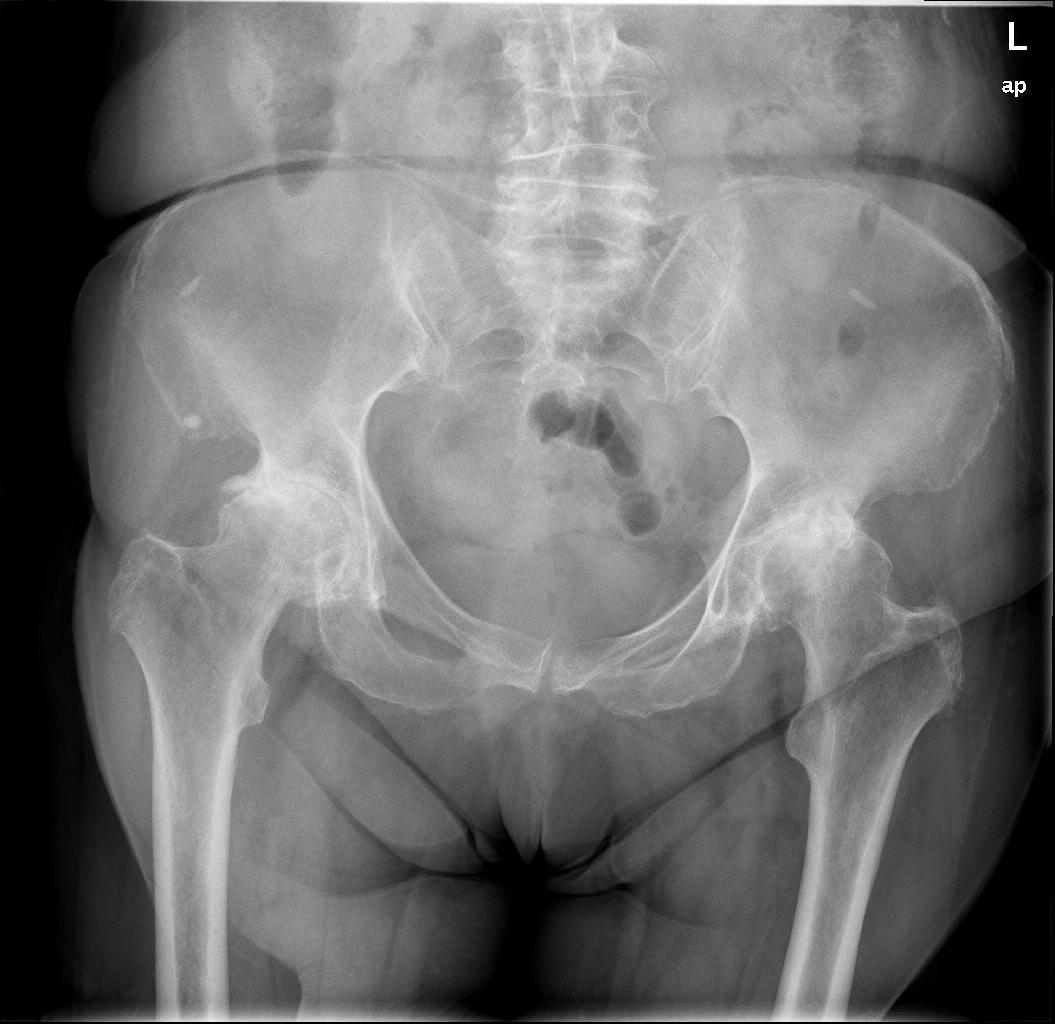

Το πρώτο βήμα κατά τη λήψη της απόφασης για την αντικατάσταση ισχίου είναι να συναντήσετε τον χειρουργό σας για να δείτε εάν είστε υποψήφιος για χειρουργική επέμβαση ολικής αρθροπλαστικής ισχίου. Ο χειρουργός σας θα πάρει το ιατρικό ιστορικό σας, θα κάνει μια φυσική εξέταση και θα ζητήσει ακτινογραφία του ισχίου σας. Ακόμα κι αν ο πόνος είναι έντονος και οι ακτινογραφίες δείχνουν προχωρημένη αρθρίτιδα της άρθρωσης, η πρώτη γραμμή θεραπείας είναι σχεδόν πάντα μη χειρουργική. Αυτό περιλαμβάνει απώλεια βάρους εάν χρειάζεται, πρόγραμμα άσκησης, αντιφλεγμονώδη φάρμακα, ενέσεις ή νάρθηκες. Εάν τα συμπτώματα συνεχιστούν παρά αυτές τις θεραπείες και με επιβεβαιωτικές ακτινογραφίες, τότε μπορείτε να εξετάσετε το ενδεχόμενο χειρουργικής επέμβασης.

Τα περισσότερα εμφυτεύματα σήμερα έχουν παρόμοια σχέδια και σχήματα, αλλά ο γιατρός σας θα καθορίσει ποια σχέδια λειτουργούν καλύτερα για το σώμα σας. Αυτά τα εμφυτεύματα είναι κατασκευασμένα από κοβάλτιο χρώμιο ή τιτάνιο. Μια μεταβλητή που παραμένει ακόμα είναι η επιφάνεια φόρτισης. Η επιφάνεια φόρτισης είναι η σφαίρα, η κεφαλή και η επένδυση που προσκολλώνται στο μηριαίο στέλεχος, και το κυπέλιο, η το κοτυλιαίο εμφύτευμα που στερεώνεται στο οστό. Η κεφαλή μπορεί να αποτελείται είτε από μέταλλο (κράμα χρωμίου κοβαλτίου) είτε από κεραμικό και η επένδυση μπορεί να είναι από πλαστικό (πολυαιθυλένιο), μέταλλο ή κεραμικό. Η κεφαλή και η επένδυση μπορούν στη συνέχεια να χρησιμοποιηθούν σε διαφορετικούς συνδυασμούς και ονομάζονται για τον αντίστοιχο συνδυασμό επένδυσης κεφαλή (μέταλλο σε πολυ, κεραμικό σε πολυ, κεραμικό σε κεραμικό κ.λπ.).